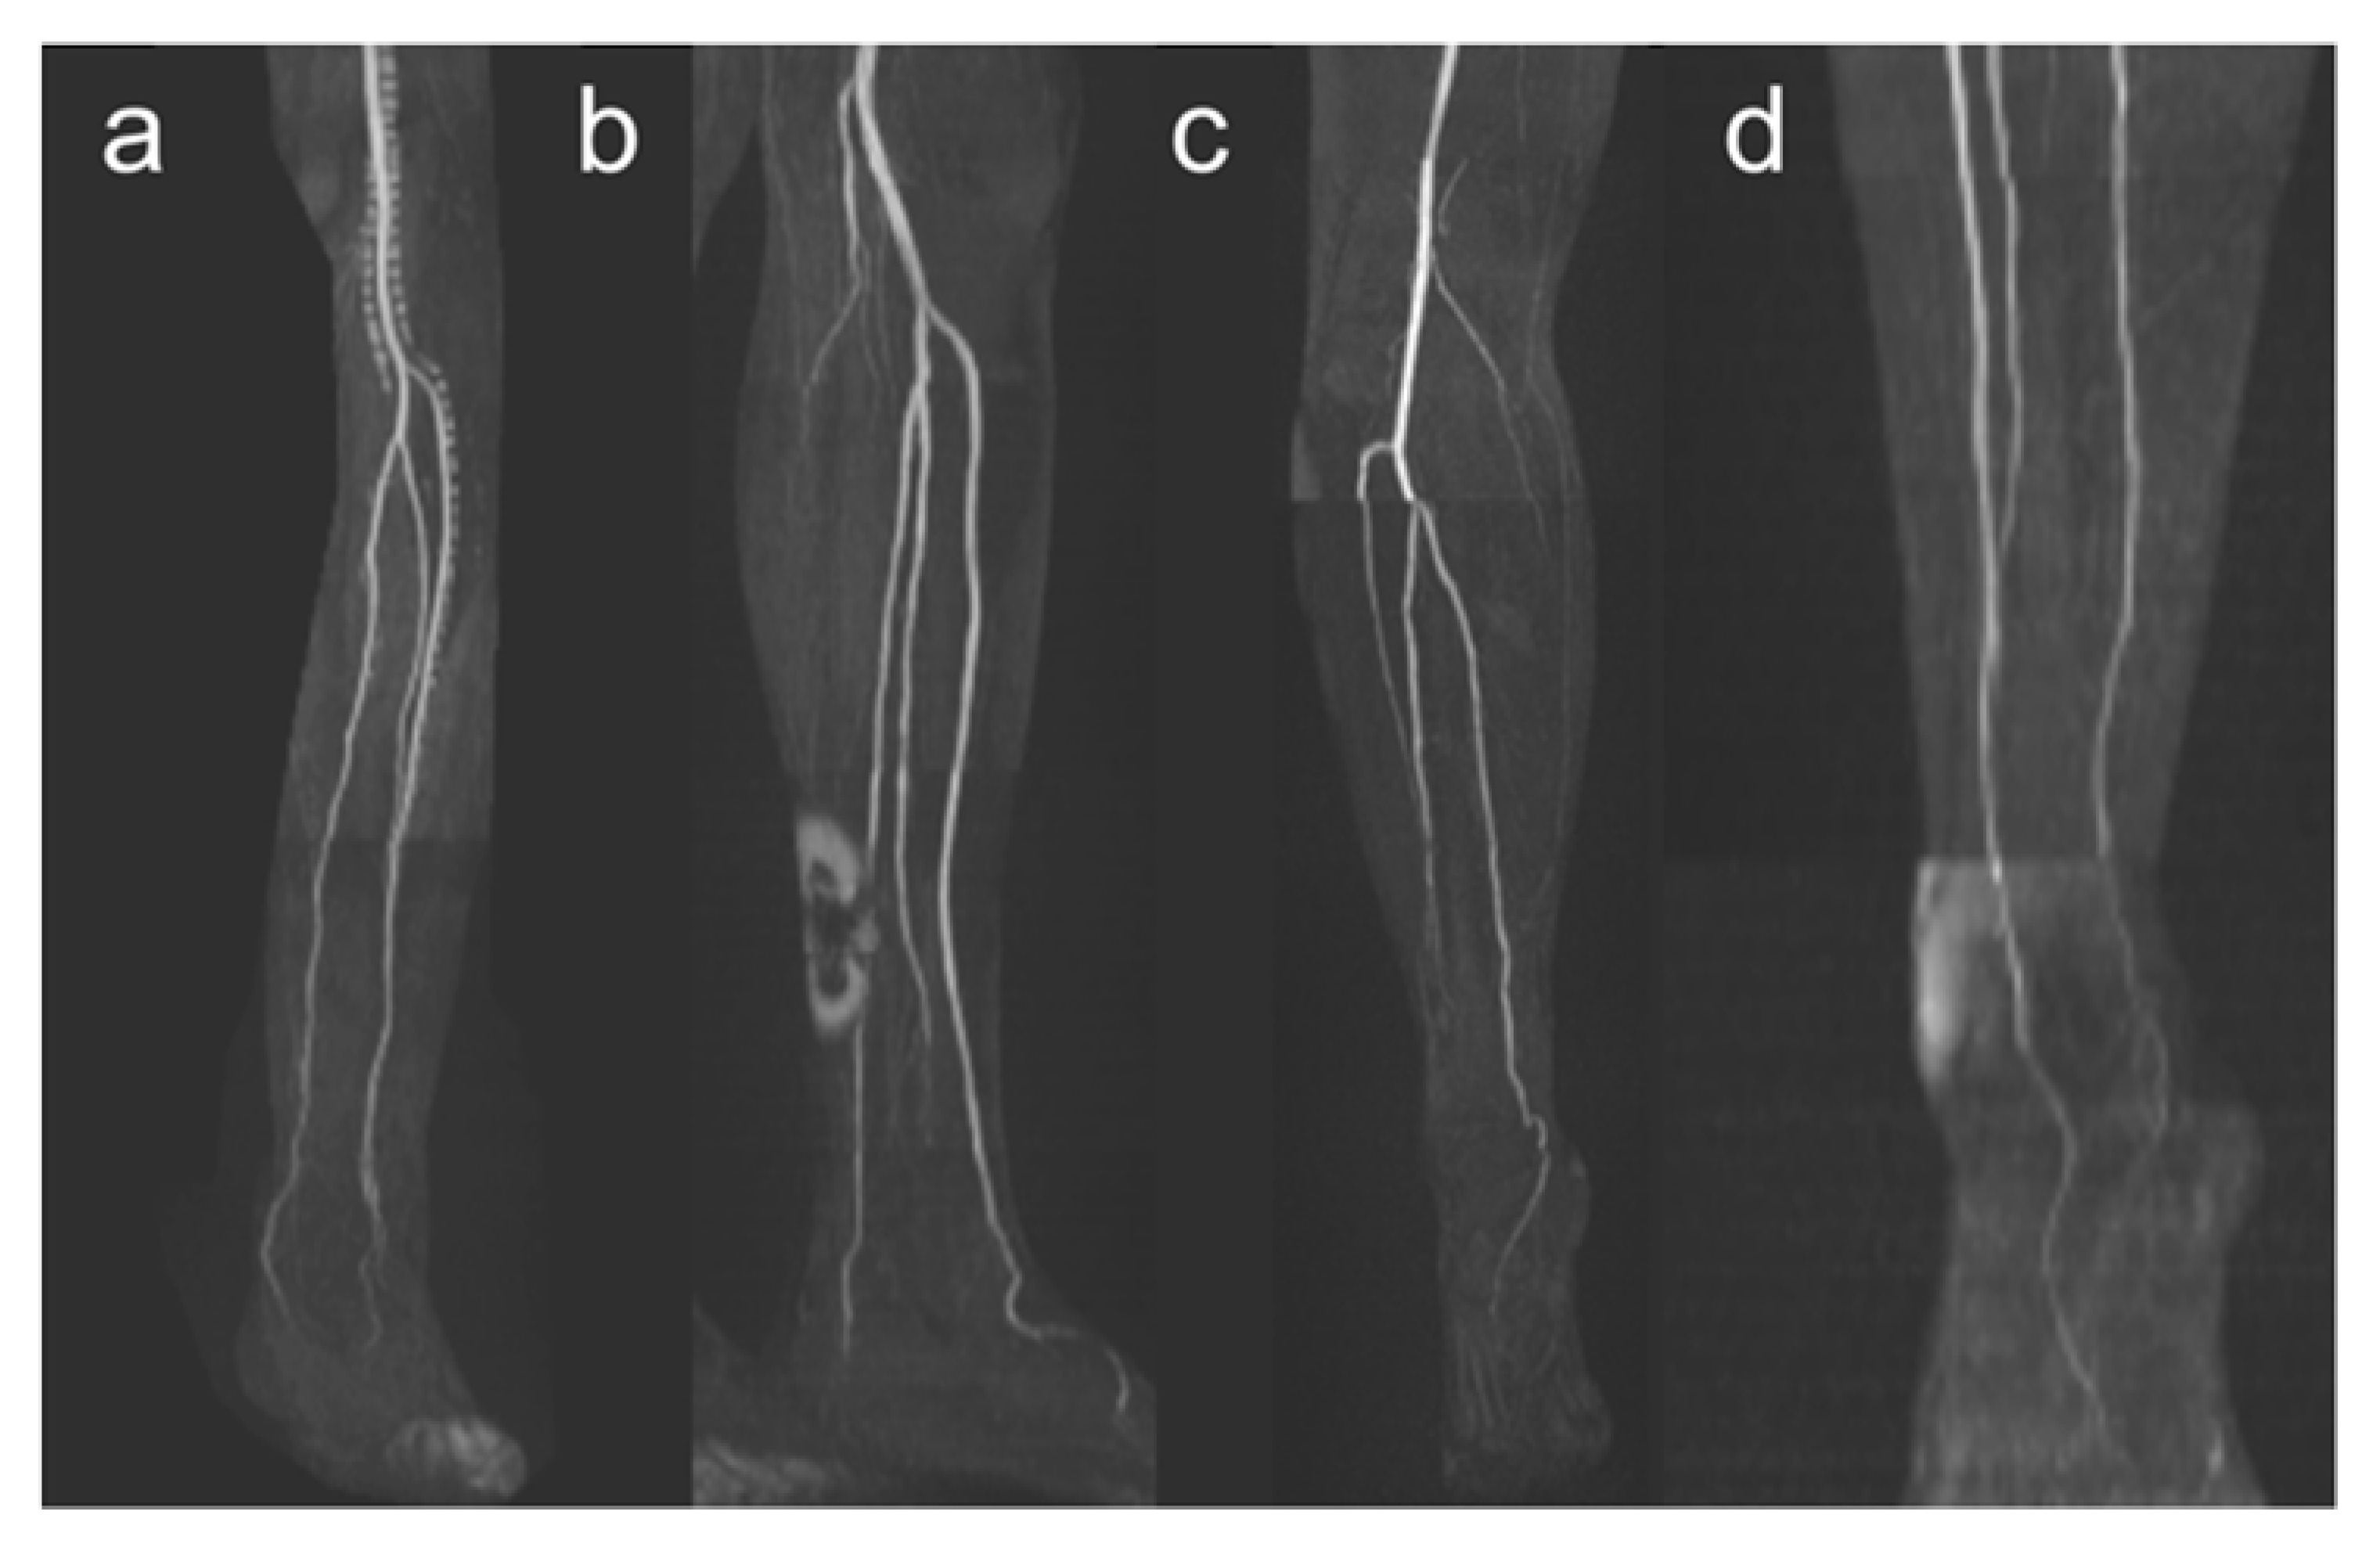

Figure 1.

Imaging artifacts. Venous contamination is shown in panel (a), signal dropouts due to endoprostheses or other metallic implants in panel (b), stair-step artifacts in panel (c), and different signal intensities within a measurement slab in panel (d). Motion artifacts are not demonstrated here because they can only be traced in the course of several transverse slices.